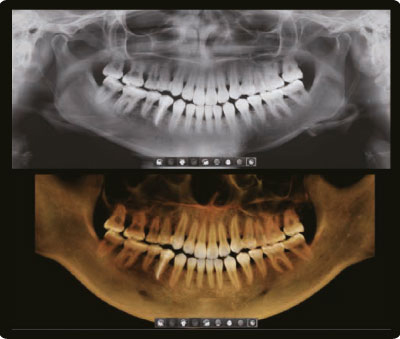

2D и 3D за одно сканирование, в одном приложении

Томограф Green X сочетает возможности компьютерной томографии и панорамной съемки, обеспечивая пациентам минимизацию облучения. Все изображения можно просматривать в едином приложении, что значительно упрощает процесс диагностики, объяснения клинической картины и разработки плана лечения.